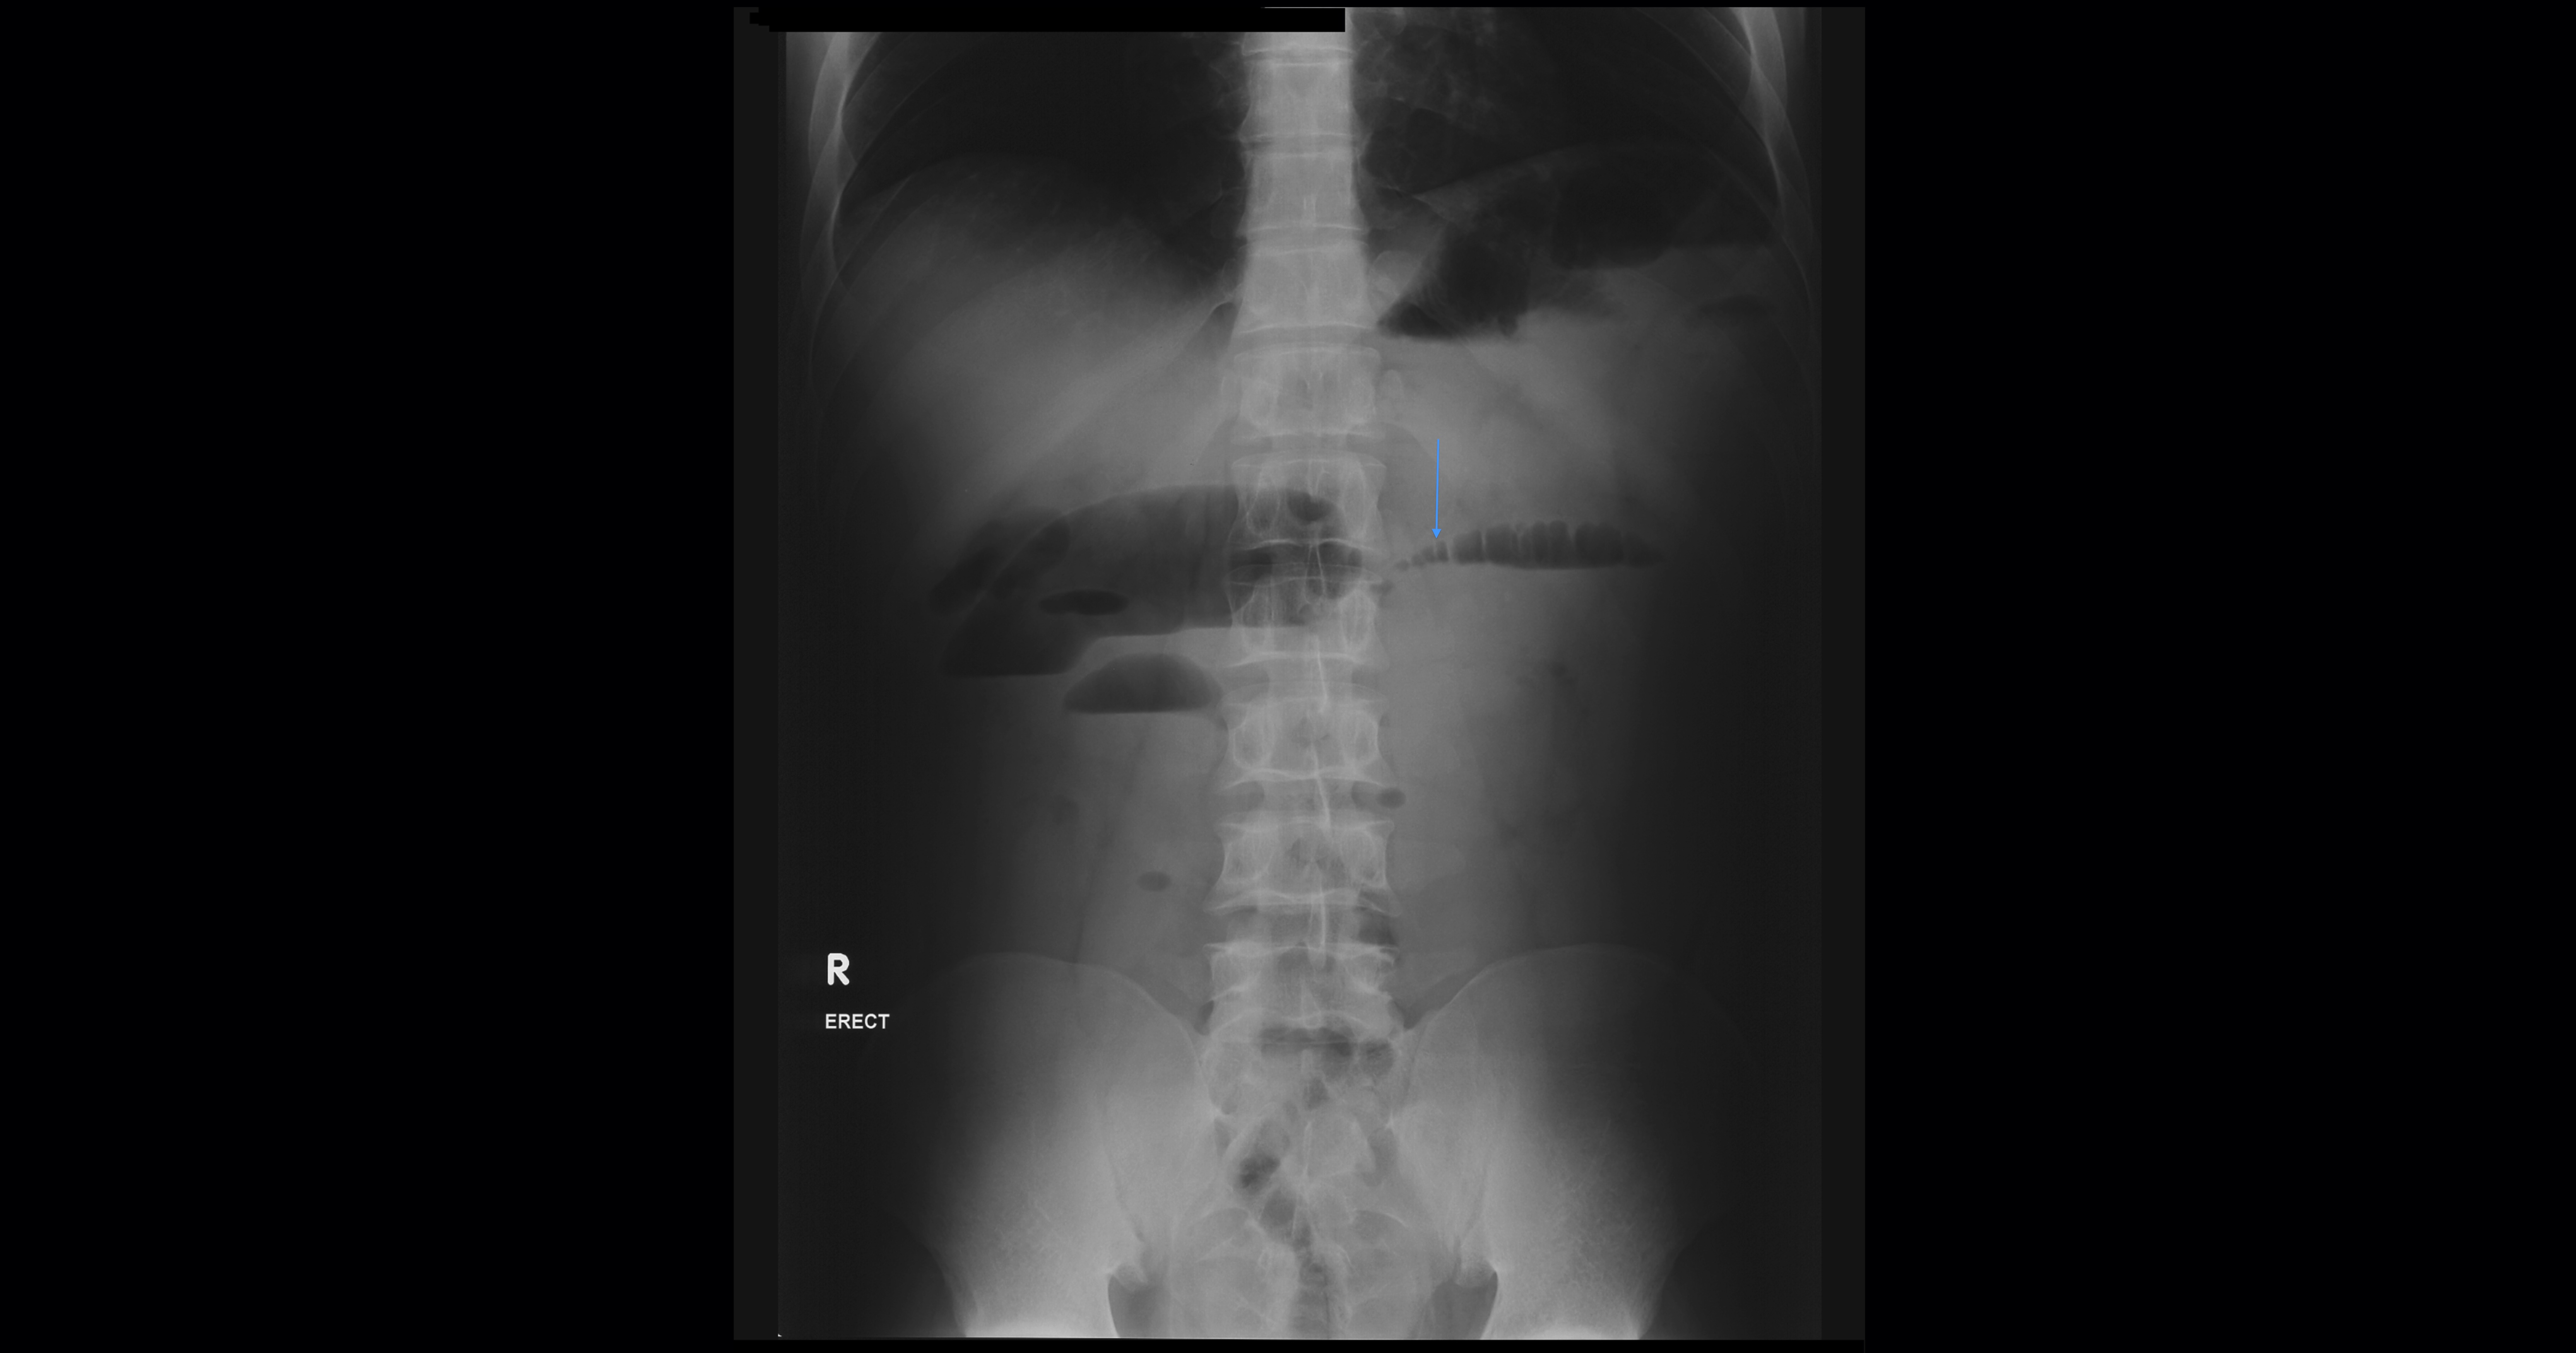

Small bowel obstruction is a common clinical presentation that presents a diagnostic conundrum. Over the last 2 decades, there has been a paradigm shift in the radiological investigation of small bowel obstruction (SBO) and in the indication for and timing of surgical intervention. Cross sectional imaging (predominantly computed tomography) has largely replaced the widespread use of radiographic small bowel follow-through studies as the imaging modality of choice for SBO. This article illustrates the current imaging modalities available for diagnosis of small bowel obstruction. (Full text available online at www.medpharm.tandfonline.com/ojfp) S Afr Fam Pract 2015; DOI: /10.1080/20786190.2014.977052